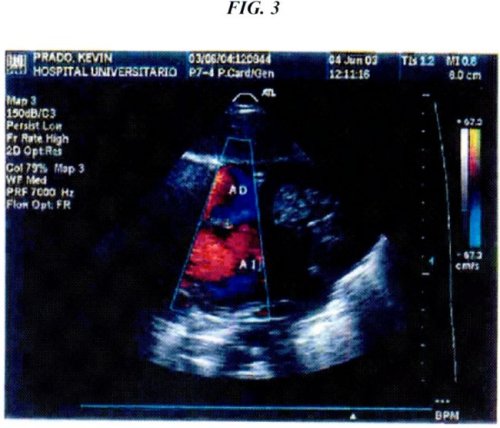

Dopler color: flujo turbulento a través de la aorta compatible con estenosis leve, flujo turbulento en tracto de salida del ventrículo y arteria pulmonar, flujo a través del tabique interauricular. Conclusión ventrículo único, estenosis pulmonar subvalvular y valvular, estenosis aórtica leve, foramen ovale permeable (Fig. 3).